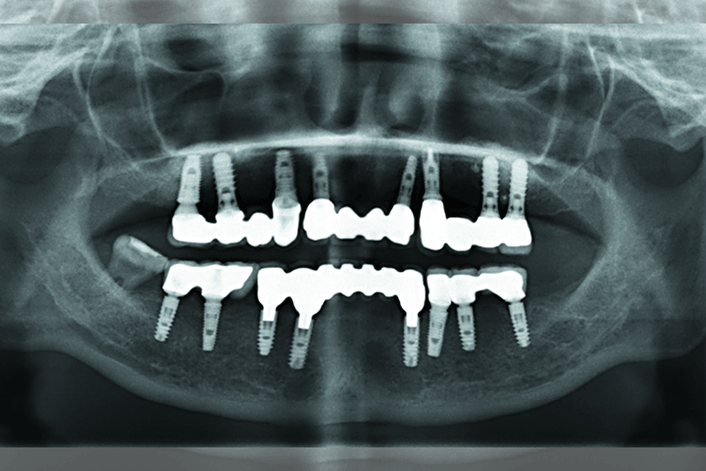

Now online in the Journal of Prosthodontics, a case report on the prosthodontic rehabilitation of a 24-year-old patient diagnosed with hypophosphatasia (HPP) at age 5.

The patient presented for implant treatment because her previous removable partial denture lacked retention and masticatory function was unsatisfactory. The report demonstrates that the exfoliation of permanent teeth can be treated by dental implant-supported fixed restorations in HPP cases.

Currently, all implants have been present for more than 7 years.